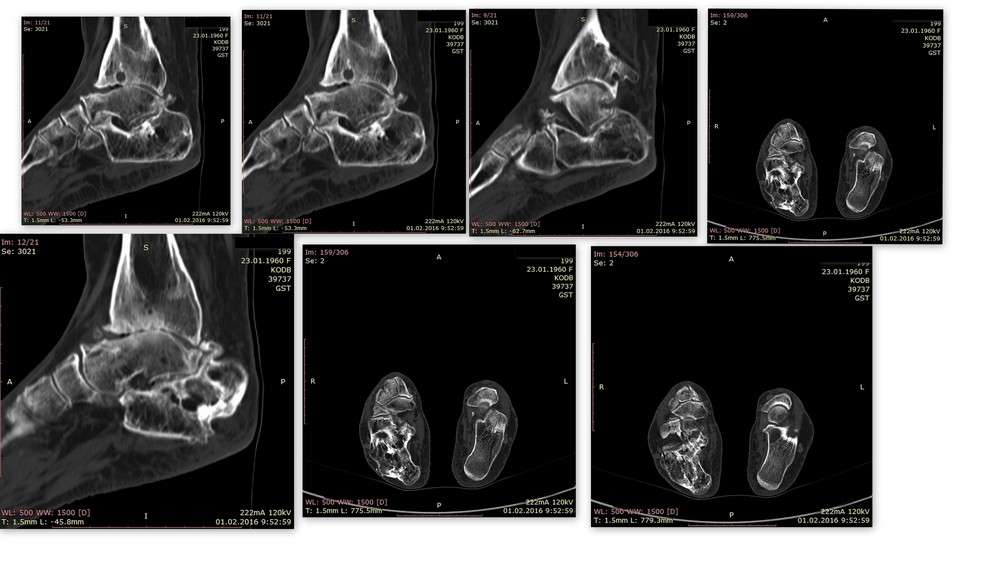

Уважаемые коллеги, прошу Вас выразить свое мнение по поводу тактики

лечения. Пациентка 56 лет -наша коллега. Травма в ДТП более 20 лет -

открытый оскольчатый перелом костей левого голеностопного

сустава,осложнившийся остеомиелитом. Лечилась скелетным вытяжение,

клиника остеомиелита купирована. На данный момент- в последние годы

беспокоит стойким болевой симптом в голеностопном суставе, купирующийся

анальгетиками на фоне регулярных блокад. Принимает варфарин. Спасибо за

помощь.